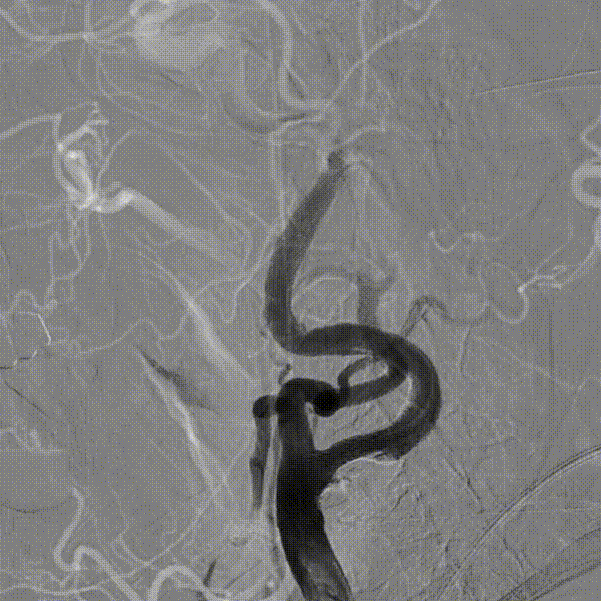

考虑到靶血管较迂曲,拟使用中间导管进行支架释放。在Workhorse导丝引导下,将中间导管通过迂曲段,经由中间导管送入8mm*40mm颈动脉支架至右侧颈内动脉狭窄处。回撤中间导管至颈总动脉后,在透视状态下准确释放支架。

造影显示残余狭窄小于30%,未进行后扩张。术后造影显示狭窄解除,支架置入部位满意,血流较术前明显改善。使用中间导管将Nav6保护伞顺利回收后,对股动脉穿刺点进行止血,患者安返病房。

Nav6由于其出色的安全性和独特的独立导丝技术,已成为CAS手术中术者常规应用的保护伞。在本病例中,由于患者颈内动脉起始处严重狭窄合并S形弯的解剖形态,使得保护伞和支架顺利到位变得挑战。在此类病变中,巧用6F中间导管并借助Nav6输送导管的有效支撑采用特洛伊木马及望远镜技术,可将保护伞顺利输送到C1远端平直处,为后续顺利治疗提供基础。